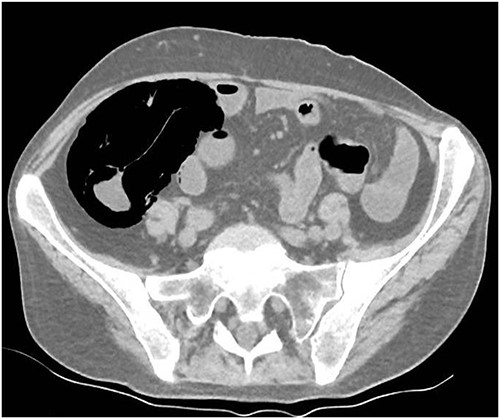

A 49-year-old female with a background of stage IV diffuse large B-cell lymphoma and subsequent chronic graft-versus-host disease (cGVHD) from a bone marrow transplant presented to a rural referral hospital in New South Wales with a 12-h history of painless per rectal bleeding and fever. She had undergone her last cycle of chemotherapy 12 months prior and her cGVHD was being treated with dexamethasone mouthwash, oral cyclosporine and an infusion of rituximab, administered the day prior to this presentation. On examination she had a soft, but distended abdomen. Laboratory investigations revealed thrombocytopenia and hypokalaemia. Computed tomography (CT) of the abdomen and pelvis had a bizarre appearance due to pneumatosis cystoides coli extending from the ileocaecal junction to the mid-transverse colon (Figs 1–3). A chest X-ray was also taken, which shows evidence transmural air within the ascending colon, including the hepatic junction (Fig. 4). Given her benign abdominal examination, her management was initially supportive with intravenous antibiotics, intravenous fluid resuscitation and correction of electrolyte abnormalities. She was subsequently transferred to a metropolitan tertiary hospital, under her usual treating haematologist with consultation by the colorectal surgical team. She recovered and did not require any acute surgical intervention for pneumatosis cystoides coli.